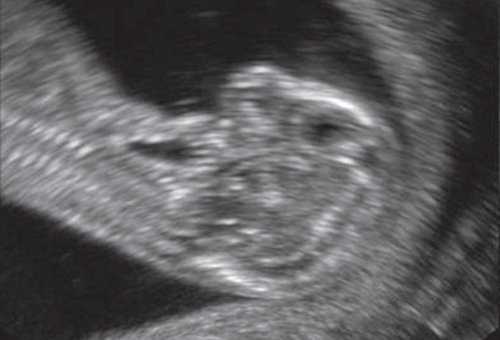

Обе ветви нижней челюсти при сроке 11-14 нед беременности выглядят гиперэхогенными, а в месте слияния имеют характерный гипоэхогенный промежуток, ультразвуковой "разрыв". Этот признак визуализируется при нормальном развитии нижней челюсти (mandibular "gap").

Размер этого промежутка уменьшается с увеличением срока беременности. Нижнечелюстной промежуток здорового плода представлен на рисунке 8.

Рис. 8. Нижнечелюстной промежуток в 13 нед беременности при нормальном развитии нижней челюсти.

При патологии нижней челюсти (микрогнатии) в срок 11-14 нед беременности при изучении коронарного скана лица нижнечелюстной "промежуток" отсутствует, нижняя челюсть представлена единой, слившейся костной массой. Отсутствие нижнечелюстного "промежутка" (mandibular "gap") при эхографии в этот срок является маркером гипоплазии нижней челюсти (микрогнатии). Варианты отсутствия нижнечелюстного промежутка при микрогнатии при различных синдромах в срок 11-14 нед беременности представлены на рисунке 9.